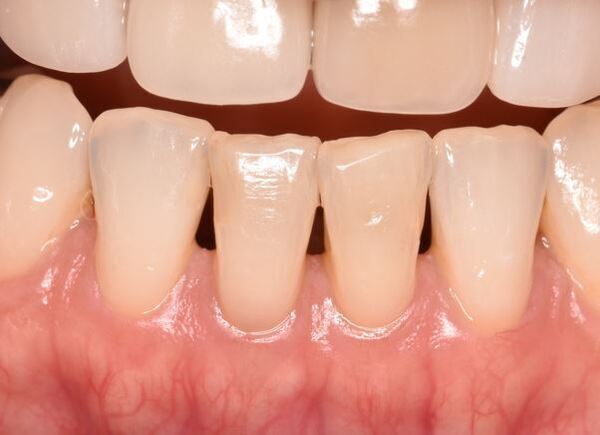

術前のレントゲン写真とCT画像と、お口の中の写真です。下の前歯2本(#31,41)です。

2本の根の周りに黒い影(透過像)があるのが分かります。

ラバーダム防湿を行い、前歯の場合は歯の裏側から穴を開けて治療を開始していきます。その際もマイクロスコープを使用しながら切削していくことで歯を無駄に削っていくことを防げます。